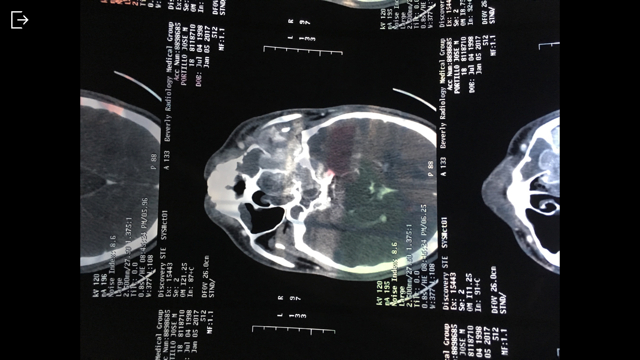

Jose Portillo is a senior in high school, who, in the winter of 2016, was diagnosed with Juvenile Nasopharyngeal Angiofibroma. This means that he has a large tumor growing in his nasal cavity, head, and neck. The tumor is growing rapidly, making it dangerous and urgent. Jose needs to be operated on immediately in order to ensure the tumor does not continue to grow into his brain.

Jose is scheduled to have his operation to remove the tumor in March, but his recovery and healing will be a long and grueling process.

To learn more about Juvenile Nasopharyngeal Angiofibroma please click the link below:

Juvenile Nasopharyngeal Angiofibroma (JNA)